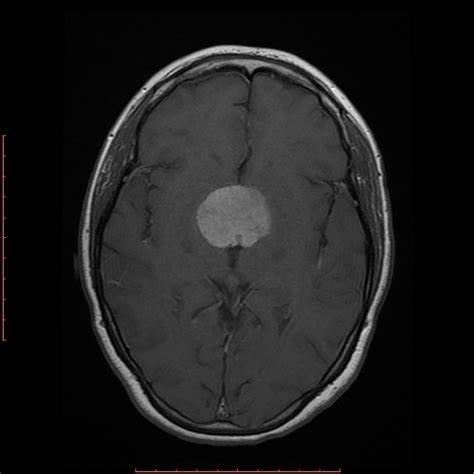

鞍結(jié)節(jié)腦膜瘤

INC國(guó)際神經(jīng)外科醫(yī)生集團(tuán)為您提供鞍結(jié)節(jié)腦膜瘤相關(guān)的前沿治療資訊、成功案例分享、熱點(diǎn)科普知識(shí)及國(guó)際教授來(lái)華信息,想了解更多鞍結(jié)節(jié)腦膜瘤資訊請(qǐng)撥打咨詢熱線:400-029-0925。

鞍區(qū)腦膜瘤的癥狀和臨床表現(xiàn)有哪些?

鞍區(qū)腦膜瘤的癥狀和臨床表現(xiàn)有哪些?鞍區(qū)腦膜瘤約占顱內(nèi)腦膜瘤的5%至10%?;颊咭耘詾橹鳎信壤秊?∶4.9:1,平均年齡50 ~ 58歲?;颊咄ǔ1憩F(xiàn)為緩慢進(jìn)行性單側(cè)或雙側(cè)視力下降。...

鞍結(jié)節(jié)腦膜瘤怎么治?鞍結(jié)節(jié)腦膜瘤患者的9個(gè)必知!

鞍結(jié)節(jié)腦膜瘤怎么治?鞍結(jié)節(jié)腦膜瘤占全部顱內(nèi)腦膜瘤的5-10%,通常起源于鞍結(jié)節(jié)硬腦膜、交叉溝和蝶緣...

鞍結(jié)節(jié)腦膜瘤手術(shù)治療新進(jìn)展:神經(jīng)內(nèi)鏡微創(chuàng)技術(shù)不斷提高

鞍結(jié)節(jié) 腦膜瘤 占全部顱內(nèi)腦膜瘤的5-10%,主要發(fā)生于鞍結(jié)節(jié)硬腦膜、交叉溝和蝶骨緣。視覺(jué)障礙是較常見(jiàn)的臨床表現(xiàn),根據(jù)Schick等人的系列報(bào)道,由于鞍結(jié)節(jié)與視器的解剖關(guān)系密切,視...

鞍結(jié)節(jié)腦膜瘤會(huì)導(dǎo)致失明嗎?

鞍結(jié)節(jié)是垂體窩前微微隆起的骨質(zhì),高度和寬度只有幾個(gè)毫米。從這個(gè)區(qū)域起源的腫瘤在引起臨床癥狀時(shí)通常直徑已達(dá)2~4cm。由于鞍區(qū)體積相對(duì)較小,這些腫瘤在硬膜上的附著處向前可伸至...